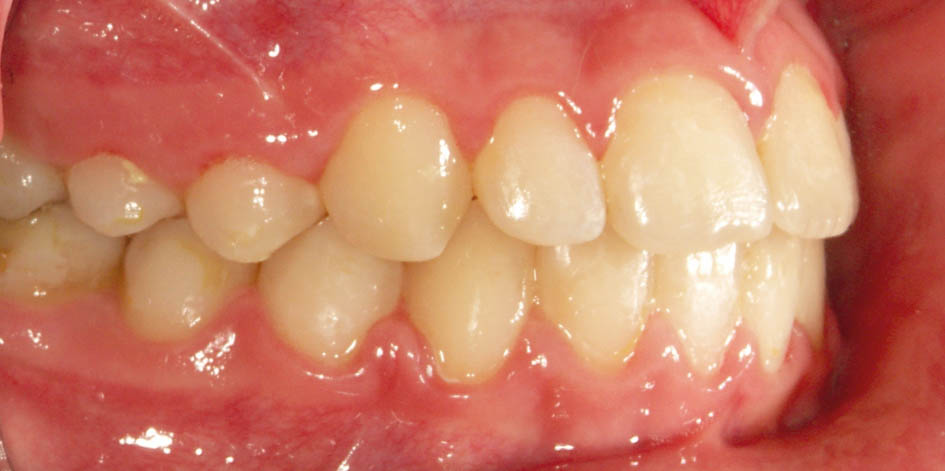

بعضی موقع چند مشکل را با هم در یک کودک میبینید. مثلاً بیمار کراس خلفی یک طرفه و کراس قدامی (شکل 36-5 و 37-5) دارد.

شکل 36-5: کراس بایت خلفی در سمت چپ

شکل 37-5: سمت راست کراس بایت خلفی ندارد پس کودک کراس بایت خلفی یک طرفه دارد.

شکل 43-5: تکمیل رویش دندانهای قدامی با اکلوژن کلاسI در سمت راست

شکل 44-5: اکلوژن کلاسI در سمت چپ